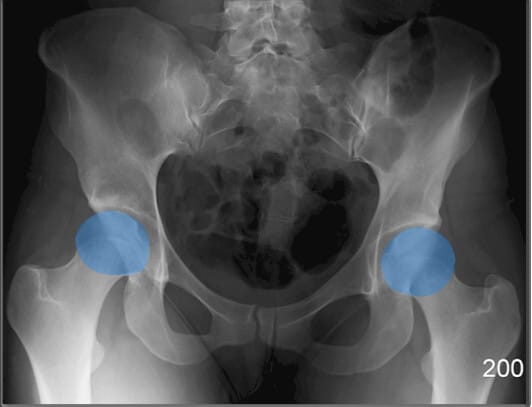

폐쇄공 (Obturator Foramen)

| 폐쇄공 (Obturator Foramen) |

| ✅ 치골과 좌골 사이에 위치한 크고 타원형의 개구부로, AP view에서는 골반 하단 양측에 대칭적인 투과성 음영으로 보입니다. |

| 🔴 골반 골절에서 비대칭이나 모양 변화가 나타날 수 있는 부위입니다. |